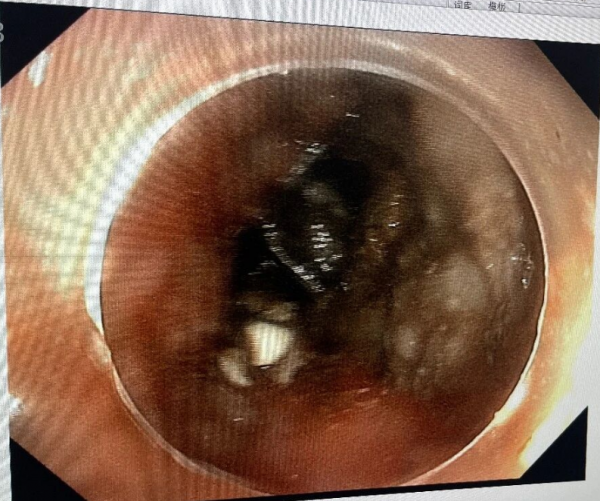

术中,张俊伟主任凭借娴熟的操作技巧,在胃镜直视下精准定位钢笔帽,利用网篮轻柔包裹异物,缓慢将其拖出。整个手术过程仅耗时15分钟,异物完整取出,患儿生命体征平稳,未出现任何不良反应。

胃镜高清成像可清晰观察异物位置及周围组织,减少误伤风险。